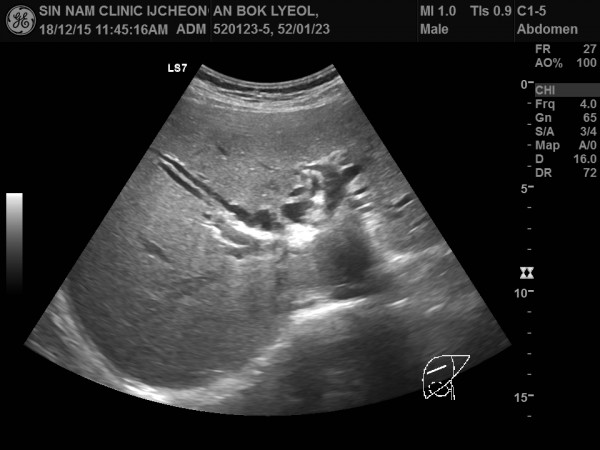

담관암, 담도암, 상복부 초음파